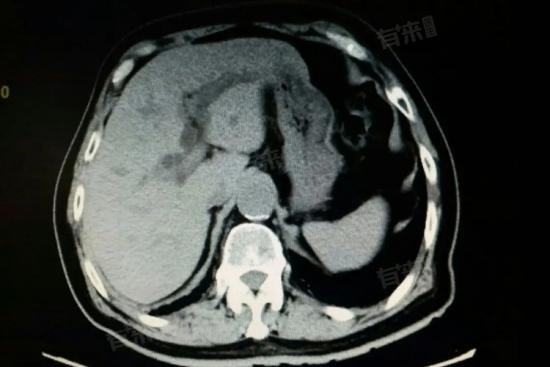

肝脏低密度灶是在肝脏影像学检查中,如CT或MRI扫描时,发现肝脏某一区域密度低于周围正常肝组织的现象,通常意味着肝脏内存在与正常肝组织密度不一致的病灶。

- 影像学检查:B型超声波检查、CT造影增强扫描、核磁共振等影像学检查是诊断肝脏低密度灶的重要手段。这些检查可以显示病灶的大小、形态、位置及与周围组织的关系,为进一步诊断提供依据。